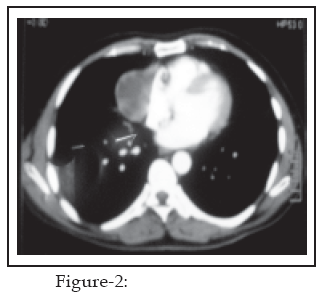

3, platelet count of 207000/mm3, serum urea at 26mg/dl, and serum creatinine at 0.9mg/dl and all electrolytes within normal range. With the suspicion of hydatid pericardial cyst in mind, Echinococcus antibody test was also sent but it came out negative (titre < 1:16).On chest X-ray a well defined homogenous soft tissue density shadow was seen in right para-cardiac region which could not be differentiated from right heart border (Fig-1). For futher evaluation, C.T. scan chest with IV contrast was done which revealed a cystic mass along side the right heart border which was projecting laterally, abutting the medial margins of the right middle lobe and measuring 6.9cm x 4.8cm. There was no evidence of either hilar or mediastinal lymphadenopathy and no mass or consolidation was seen in both lungs (Fig-2).

7,8 Our patient was fortunate that the pericardial cyst was discovered before it would have resulted in any of the complications. Although pericardial cysts have been regularly discovered through chest X-ray and echocardiogram, yet C.T. scan chest with contrast remain the investigation of choice for diagnosis2,5 where the cysts appear as non-enhanced, thin-walled, crisply defined and homogenous structures near the pericardium and are mostly found at the right cardio-phrenic angle.4,7The chest X-ray of our patient revealed findings (homogenous density at right heart border) that is similar to that seen in majority of cases. The echocardiogram report indicated normal heart function and it was only through C.T. chest with contrast that one was able to appreciate the size, septations and further structural details that lead to the diagnosis of pericardial cyst.